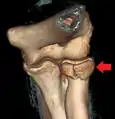

Radial head fracture

Radial head fractures are diagnosed from a clinical assessment and diagnostic imaging. Clinical assessment may include pain or tenderness at the radial head, bruising, swelling, and a limited range of motion of the injured elbow.[2] Diagnostic imaging may include ultrasound, plain radiography (x-ray imaging), Computed tomography scan (CT), and magnetic resonance imaging (MRI).[2][4] A fat pad sign may be present on diagnostic imaging and may indicate a radial head fracture.[5]